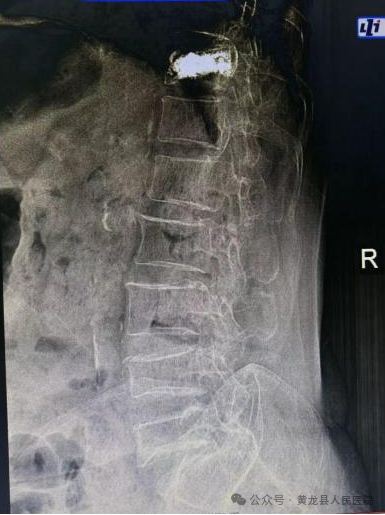

患者女,78岁,2023年3月不慎摔倒致胸腰背部疼痛,翻身、弯腰、下地活动严重受限。入院后X线检查示:腰1椎体压缩性骨折,结合患者具体情况,给予综合评估,给予微创经皮椎体成形手术,手术效果满意。2023年8月,患者再次不慎摔伤,致胸11椎体骨折,有了第一次微创手术经历,患者入院后果断选择微创经皮椎体成形手术治疗,手术顺利,达到预期效果,术后患者恢复较好,经过外科医护团队精心治疗和优质护理,患者顺利出院。患者及家属对整个就医感受很是满意,特送上锦旗向医务人员表示感谢。

术前MRI 和术后X线影像图片